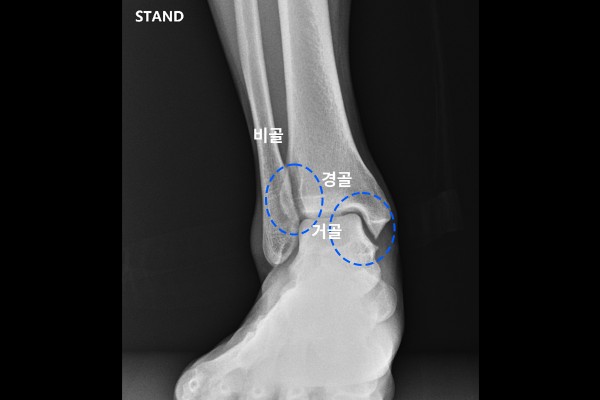

환자분의 발목 상태 파악을 위해 X-RAY 사진을 살펴보면, 먼저 증상이 없는 오른쪽 발목은 발목관절의 내측 공간이 벌어지지 않았고, 아래 거골과 위쪽 경골 부분이 딱 맞아 보이고, 경골과 비골 사이에 겹치는 부분이 정상적으로 확인됩니다.

반면, 통증이 있는 왼쪽 발목은 내측 공간이 벌어져있는데, 이는 삼각인대가 파열됨을 의심할 수 있습니다. 또한 경골과 비골이 겹치는 공간도 우측 발목에 비해서 작아진 것이 확인됩니다. 경골과 비골이 겹치는 부분이 작아졌다는 것은 원위경비결합인대 부분이 손상된 것으로 확인됩니다.